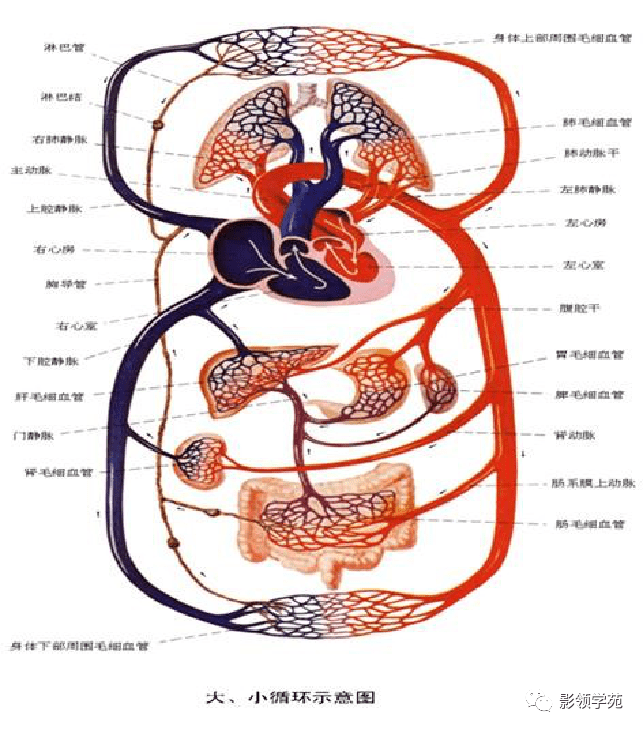

心血管系统

心血管系统